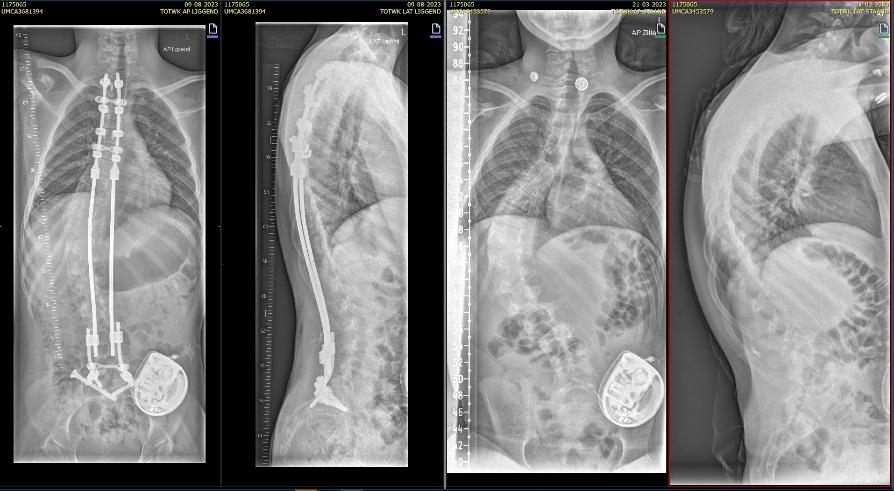

Als de voorbereidingen klaar zijn begint de operatie. De orthopedisch chirurg hangt kleine gewichtjes aan je benen en hoofd zodat je goed recht ligt. Hiervoor plaatsen we een klem net boven je oren, na de operatie is deze weer verwijderd maar heb je twee kleine gaatjes.. De orthopedisch chirurg maakt een of twee wond(en) op de rug. Tijdens de operatie maakt de chirurg de bocht in jouw wervelkolom zo recht mogelijk. De wervelkolom wordt vastgezet met behulp van titanium staven (of kobalt chroom) en schroeven of haakjes.

Bij neuromusculaire scolioses wordt er over het algemeen gekozen voor een “bipolair systeem”

Bij deze operatie zetten we de wervelkolom vast door middel van 2 verankeringspunten aan de ruggenwervels, boven tussen de schouderbladen en onder in het bekken. Hiervoor maken we een wond tussen de schouderbladen, onderin bij de lage rug, en ter hoogte van het bekken 2 kleine wondjes. De twee verankeringspunten verbinden we met elkaar door een metalen staaf onder de huid te schuiven. Met de staven kunnen we de rug rechter maken.

Rontgen foto voor (links) en na (rechts) scoliose correctie